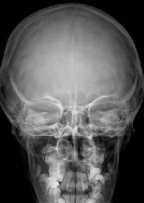

Visible Anatomical Structures

Frontal Bone

Complete frontal region

Crista Galli

Ethmoidal process

Ethmoidal Cells

Posterior ethmoidal

Petrous Bones

Temporal petrous portion

Temporal Bones

Image Quality

Perfect symmetry, sharp bone borders, visible diploe.

PA Skull vs Caldwell

PA SKULL

Angulation: 0° (perpendicular)

Visualization: Diploe, sutures

Indication: General bone study

CALDWELL

Angulation: 15° caudal

Visualization: Frontal sinuses, orbits

Indication: Facial trauma, sinuses